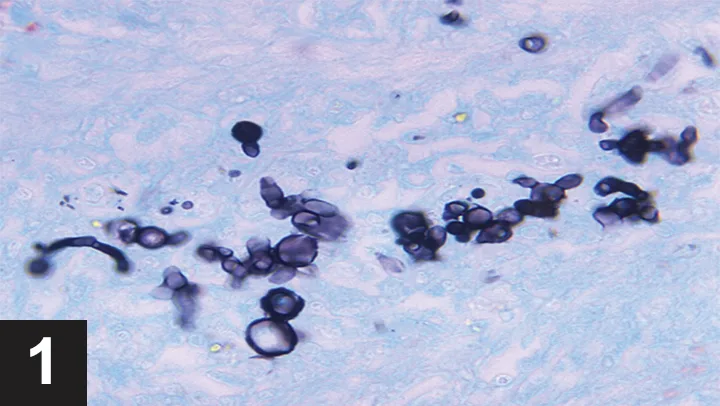

Cytology results were suggestive of blastomycosis based on the presence of abundant budding yeasts with a broad base (Figure 1). On further consultation, the owner revealed that Sadie regularly accompanies her on camping trips to an area near Georgian Bay, Ontario, where blastomycosis is endemic.

FIGURE 1

Blastomyces dermatitidis from a liver aspirate in a dog with blastomycosis. Note the typical budding yeasts. Image courtesy of Centers for Disease Control and Prevention—National Center for Zoonotic, Vector-Borne, and Enteric Diseases; Division of Foodborne, Bacterial and Mycotic Disease